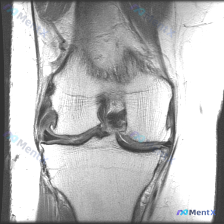

刚整理了一个有意思的读片病例,临床和影像表现有点冲突,分享一下完整分析思路: 病例基础信息 这是一张膝关节MRI冠状位T1加权成像(T1WI),用户提示观察内容为「软骨异常」。 影像读片结果 先给大家说清楚各个结构的观察情况: 1. 骨骼结构:股骨远端、胫骨近端显示清晰,骨皮质低信号、骨髓腔中等信号...